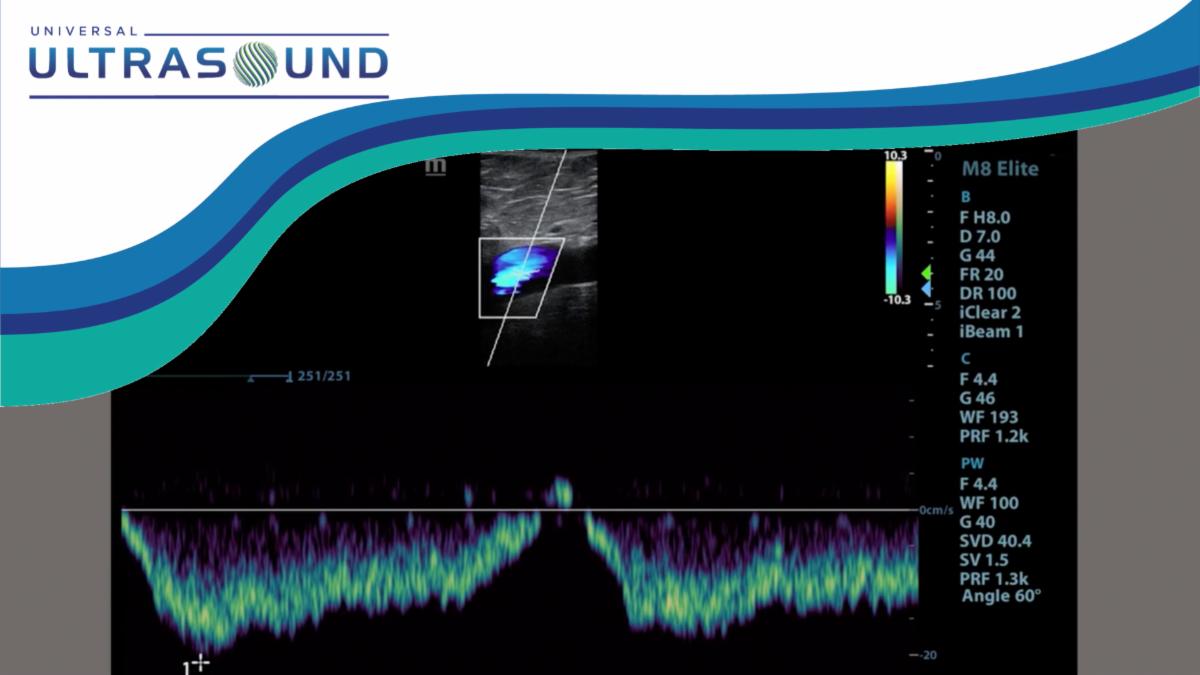

Teaching Tidbit: Right Iliac Vein Compression

Due to her clinical presentation and recurrent symptoms, a ultrasound of the outflow veins was ordered by the physician...

ILIOCAVAL VENOUS ULTRASOUND COURSE